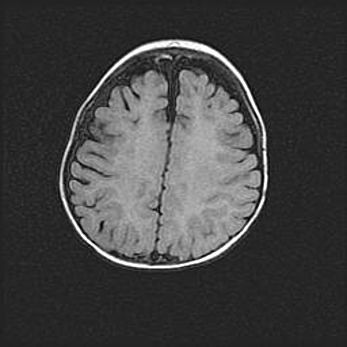

Церебральная ишемия II.

Возраст: 5 дней

Вес: 3400 г

Пол: женский

Окружность головы: 35 см

Срок гестации: 39 недель

Церебральная ишемия – это заболевание, характеризующееся недостаточностью (гипоксией) либо полным прекращением (аноксией) снабжения мозга кислородом по причине закупорки одного или нескольких сосудов. Это приводит к  что метаболическим расстройствам различной степени тяжести в тканях головного мозга, развитию коагуляционных некрозов и гибели нейронов.